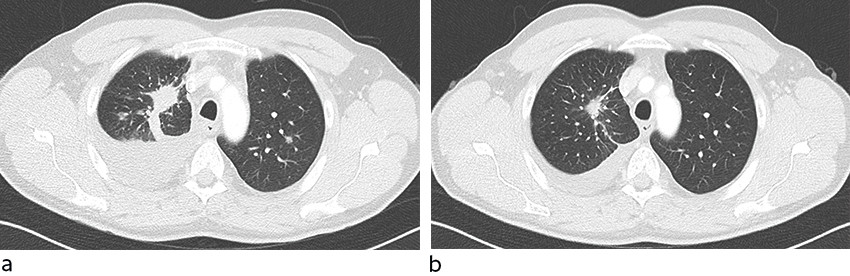

Pasienten har senere blitt fulgt ved vår seksjon og har mottatt ny forsyning av medisiner ved regelmessige oppmøter på det utenlandske sykehuset. Han merket bedring av symptomene allerede etter få dagers behandling, og rundt seks uker senere var han helt symptomfri. CEA-nivået falt fra 1021 til 705 µg/L (0 - 5 µg/L) i løpet av et par uker, og fortsatte deretter å falle raskt (figur 1). Etter to måneders behandling viste CT toraks skrumpning av tumor og tilbakegang av pleuravæske (figur 2). Han har ikke hatt bivirkninger av behandlingen.